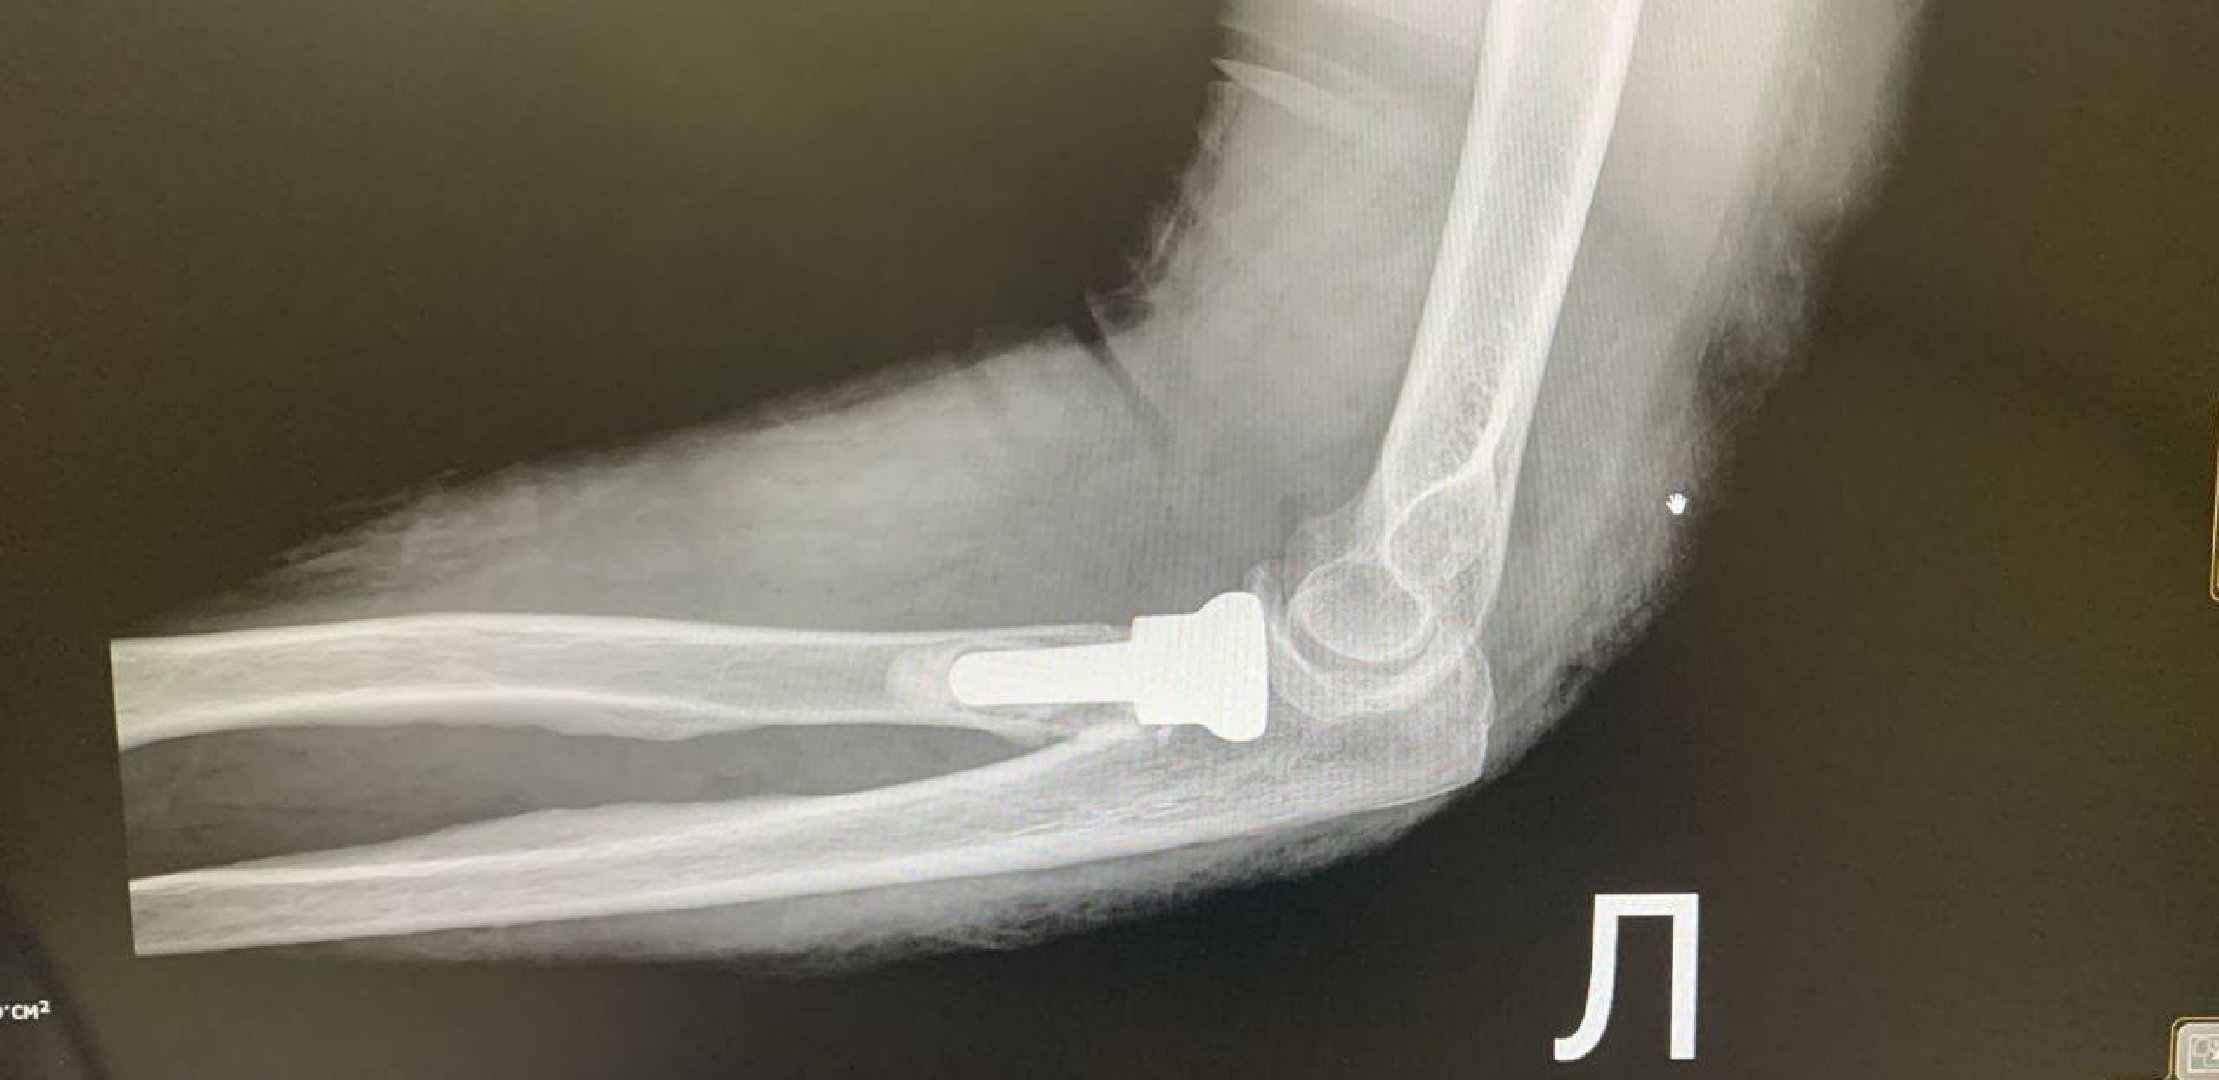

«При таких травмах крайне сложно стабилизировать перелом пластинами – выполнить так называемый остеосинтез. Поэтому было решено провести протезирование головки лучевой кости. Такое вмешательство требует высокой точности и опыта врачей. Во время операции удаляются костные осколки и устанавливается эндопротез лучевой кости», – объяснил заведующий травматологическим отделением Тавриз Аббасов.

Преимущество этой методики – полное восстановление функции локтевого сустава в кратчайшие сроки. После операции пациенты могут без ограничений сгибать, разгибать и руку и вращать ею.